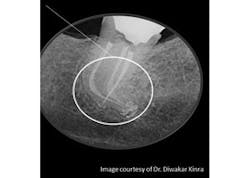

Successful root canal therapy is dependent on many factors, based on decisions made by the clinician from start to finish of each case. There are many different obturation techniques; no one technique has been identified as clearly superior. Dr. Diwakar Kinra, editorial director of DE’s ENDO File, talks through the concept of obturation in endodontics and shares his insight into the ongoing controversy. Click here to read the article